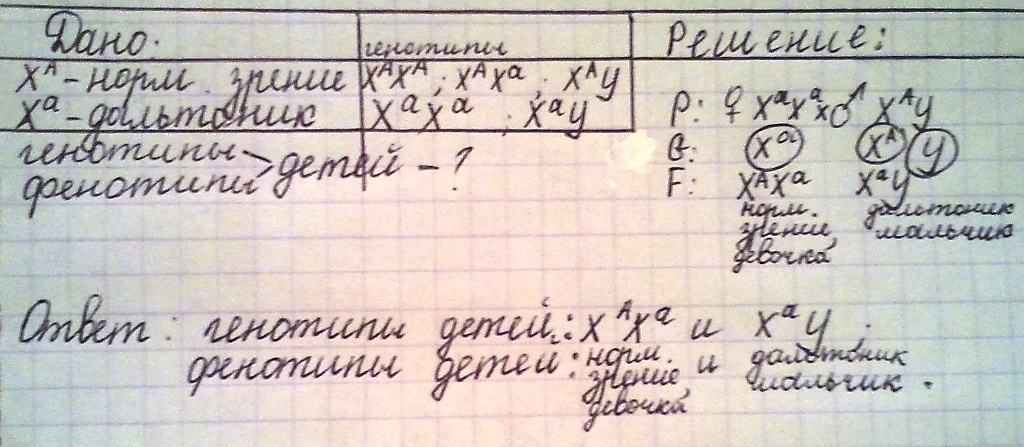

Генетика гемофилии: рецессивные гены и их проявления